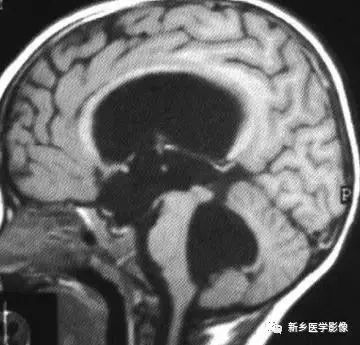

8.胼胝体发育不良

在脑发育腹侧诱导晚期,新形成的端脑嘴侧壁的背侧部分增厚、内陷,向后沿尚未完全发育的大脑半球间裂延伸。两个月后形成一个连合即胼胝体纤维的细胞框架,该细胞框架形成后胼胝体相应部分立即发育。膝部先发育。然后是体部、压部.位于胼胝体膝部后下方的胼胝体嘴最后发育。如果胼胝体发育过程中出现有害因素,就有可能导致胼胝体发育不良.表现为完全缺如或部分缺失。常表现为膝部存在或膝部和体部存在。压部和胼胝体嘴缺失。

胼胝体发育不良可见单独发病,但更常见的是伴有中枢伸经系统的其他畸形,包括胼胝体周围脂肪瘤、脑膨出、交通性脑积水Chaiarii畸形、Dandy-Walker囊肿、脑裂畸形等。临床上可无症状或仅有轻度临床症状,临床检查可见眼距过宽、大头畸形、智力发育迟滞等。胼胝体缺失时,MR冠状位上侧脑室前角呈新月形表现,侧脑室体部分离,呈垂直状平行走行。